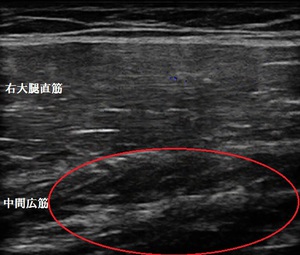

右大腿部 超音波長軸像 右同部 短軸像

鶴ヶ島市若葉 30代男性会社員。 もも(大腿部)の痛み、打撲。

超音波検査をしたところ、中間広筋が打撲により挫滅し内出血と浮腫が認められました(左右画像の

赤丸内)。